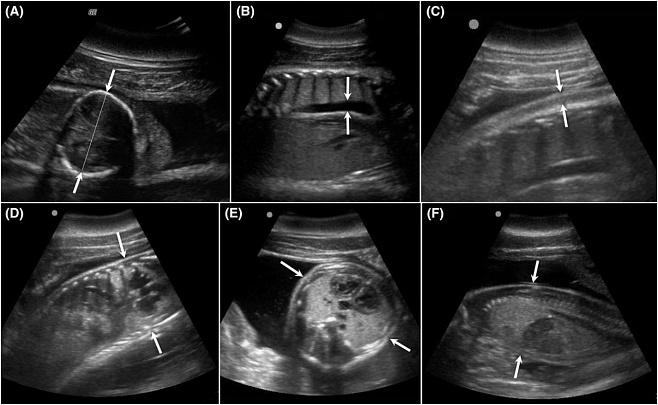

У людей и некоторых видов животных УЗИ неоднократно доказывало способность сохранять жизнь как матери, так и плода. У дельфинов с помощью этой технологии удавалось изучать легкие, сердце, печень, мочеполовую, пищеварительную и лимфатическую системы организма. Теперь же специалистам NMMF удалось усовершенствовать технологию для проведения УЗИ-мониторинга беременности дельфинов-афалин – с 2010 по 2016 годы команда исследователей наблюдала за 16 здоровыми беременностями. Несмотря на относительно маленькое число участников исследования, удалось получить свыше 200 снимков и с их помощью установить около 70 параметров, которые в дальнейшем помогут в определении состояния эмбриона и плаценты. На основании полученных данных ветеринары смогут диагностировать врожденные аномалии на ранних сроках.